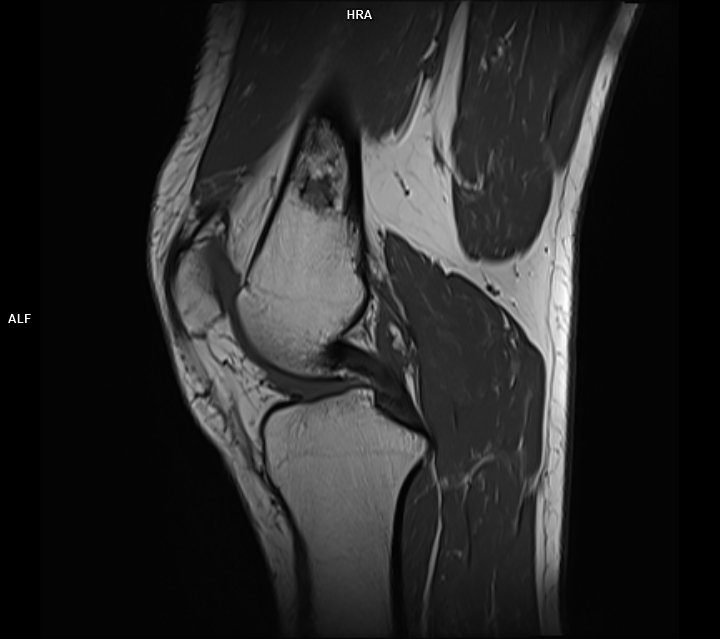

Figura 2, 3: achiziție T1 sagital